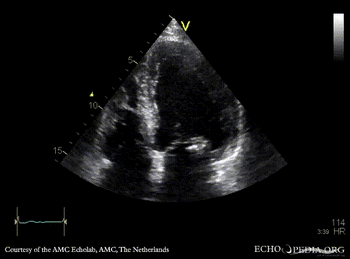

| Courtesy of: AMC Echolab, AMC, The Netherlands | |

| PLAX: vegetations on PMVL | A4CH |